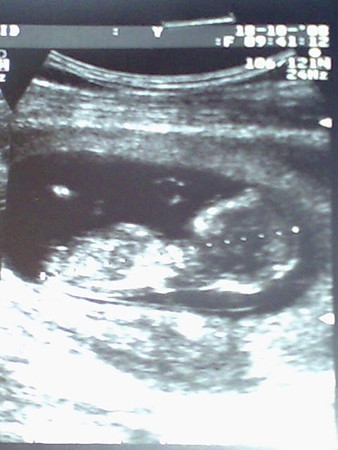

Моя малявочка и наше узи!

В субботку я решила пойти и сделать платное узи для скриннинга,я уже знала.что у моего малыша уже сформирована большая часть всего его тельца и что он уже шевелится,но всё это знала по прочтению инфы в интернете и по дневникам бэбибложек...

...Утром я без труда встала вдохновлённая тем,что сегодня увижу свою лялю,но я даже и подумать не могла какое же это ощущение счастья когда врач показывает на монитор,а там карапуз,который в последний раз был непонятное крупинкой уже человечек,мой родной маленький,живущий во мне человечек...

...Это состояние не описуемого счастья когда ты видишь как он уже во всю там шевелиться,когда врач приближает изображение на мониторе и показывает тебе его ручкой,которой он шевелит и на ней уже сформированы все пальчики и малюсенькие ножки с пальчиками,которыми он так и шевелит...

Маленький мой пузожитель если б ты только знал,как я и твой папочка любим тебя и ждём! Ты у нас самый самый замечяательный!!!

Кажеться что целого мира мало что бы умистить своё счастье!

Врач нам сказал,что развмваемся мы хорошо и что всё у нас хорошо)))

а вот и моя ляля!